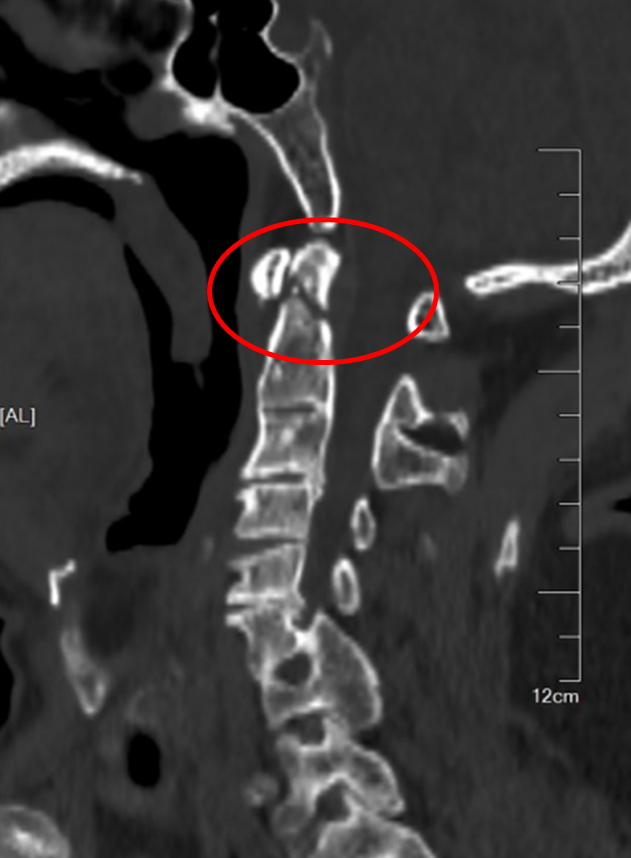

图1:术前CT和MR

患者侯师傅在工地作业中不幸被坠落的钢筋重重砸中颈部,致使四肢完全无法活动。紧急送医后,查体显示其四肢肌力仅为0-1级,处于近乎全瘫的状态。完善影像学检查提示:枢椎齿状突骨折并向后倾倒,严重压迫脊髓;同时合并有严重的颈椎发育畸形及多处先天性融合。脊髓的严重受损使侯师傅的生命岌岌可危,手术减压固定刻不容缓。